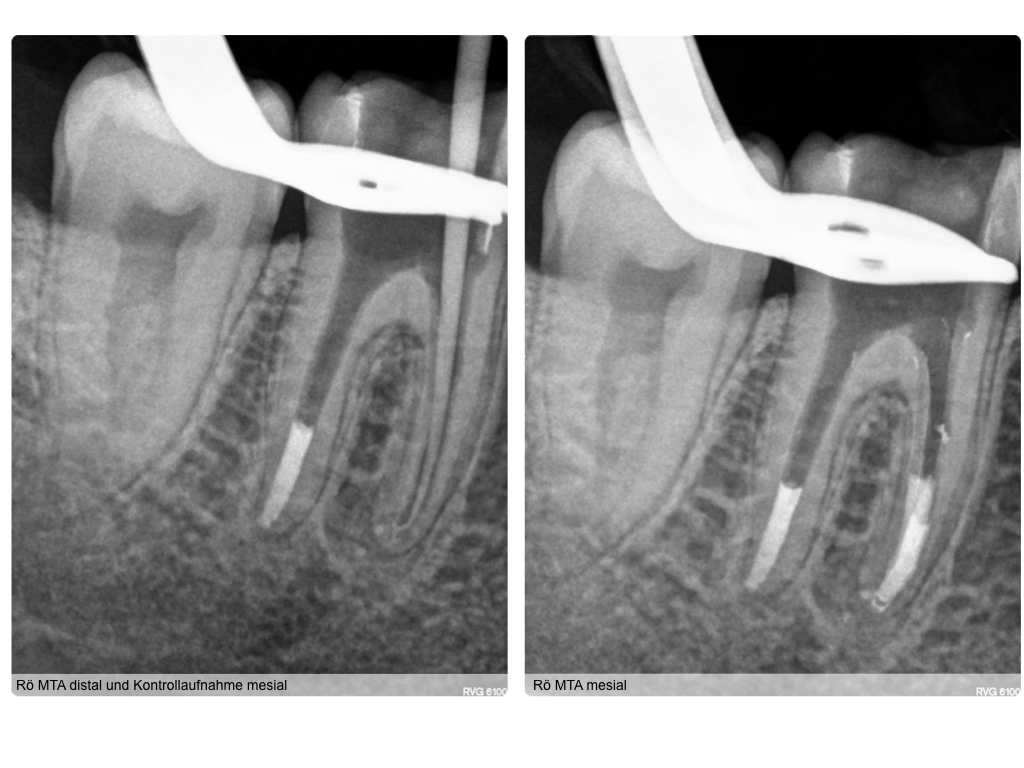

WS 16062016.005 Veröffentlicht 14. Juni 2016 am 1024 × 768 in Persistierende Schmerzen nach Wurzelkanalbehandlung